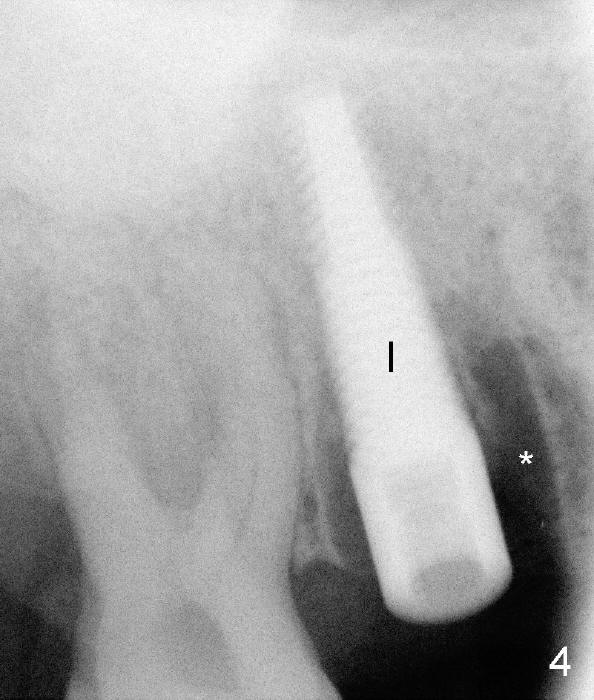

A 51-year-old man requests taking care of hemorrhage and odor associated with the tooth #3 (Fig.1). Due to religious and financial issues, the neighboring teeth will be treated later (supraeruption of #2 (arrow) and periapical radiolucency of #4 (*)). CBCT reveals that the septum of #3 is large enough to hold 4.5 mm implant (Fig.2). In fact osteotomy is created as planned in the septum using drills and taps (Fig.3 after removing 4.5x20 mm tap). Primary stability is obtained with a 4.5x20 mm implant (> 60 Ncm, Fig.4). The gap (*) is bone grafted; an abutment is placed (Fig.5 A); an immediate provisional is fabricated and cemented to cover the socket (Fig.6 P). When the socket heals in 3 weeks postop, the provisional and the abutment are removed for easy oral hygiene. Bone regenerates around the implant 3.5 months postop (Fig.7 *), but the 2nd molar has shifted mesially (arrow), presenting a restoration challenge.